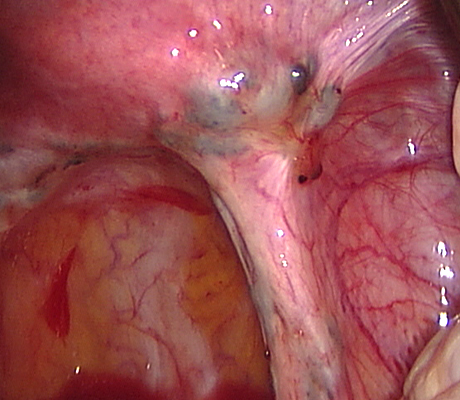

Endometriosis is a non-cancerous condition where the endometrial tissue or womb lining which normally grows only in the uterus is found in other parts of your pelvis, for example the ovaries, fallopian tubes, rectum, bladder, appendix and pelvic walls. This womb lining that grows outside the uterus responds also to hormones but at the time of your periods it can not be expelled (as the womb lining) and causes pain, cysts in the ovaries (called chocolate cysts), inflammation in your pelvis, scar tissue, pain with sexual intercourse, chronic pelvic pain, pain when passing bowel motions, lower backache, symptoms similar to urinary tract infections, premenstrual discomfort, etc.

Laparoscopy is an operation (keyhole surgery) conducted under general anaesthesia. A telescope is introduced into a small incision in your navel, other small incisions are made for using special laparoscopic instruments and all the pelvic organs are examined with magnification (Video-laparoscopy) ; then the endometriosis is treated. Video Laparoscopy allows conservative surgery (hysterectomy is NOT the usual treatment for endometriosis) which means laparoscopic excision of the endometriotic implants, with restoration of the normal anatomy and preservation of the uterus, tubes and ovaries.

There are a number of ways as endometriosis may cause infertility. Although women with mild endometriosis may get pregnant, endometriosis is usually a progressive disease, as it gets worse with time. So early diagnosis and treatment is important. Women with advanced disease have low chance of achieving a spontaneous pregnancy. There is plenty of evidence based medicine showing that laparoscopic treatment of endometriosis does improve fertility. When a patient has an ovarian endometriotic cyst associated with infertility, laparoscopic surgery is the first line of treatment. The average pregnancy rate reported after surgery in these cases is 35-50%. So laparoscopic surgery provides a woman with good chances of becoming pregnant spontaneously.